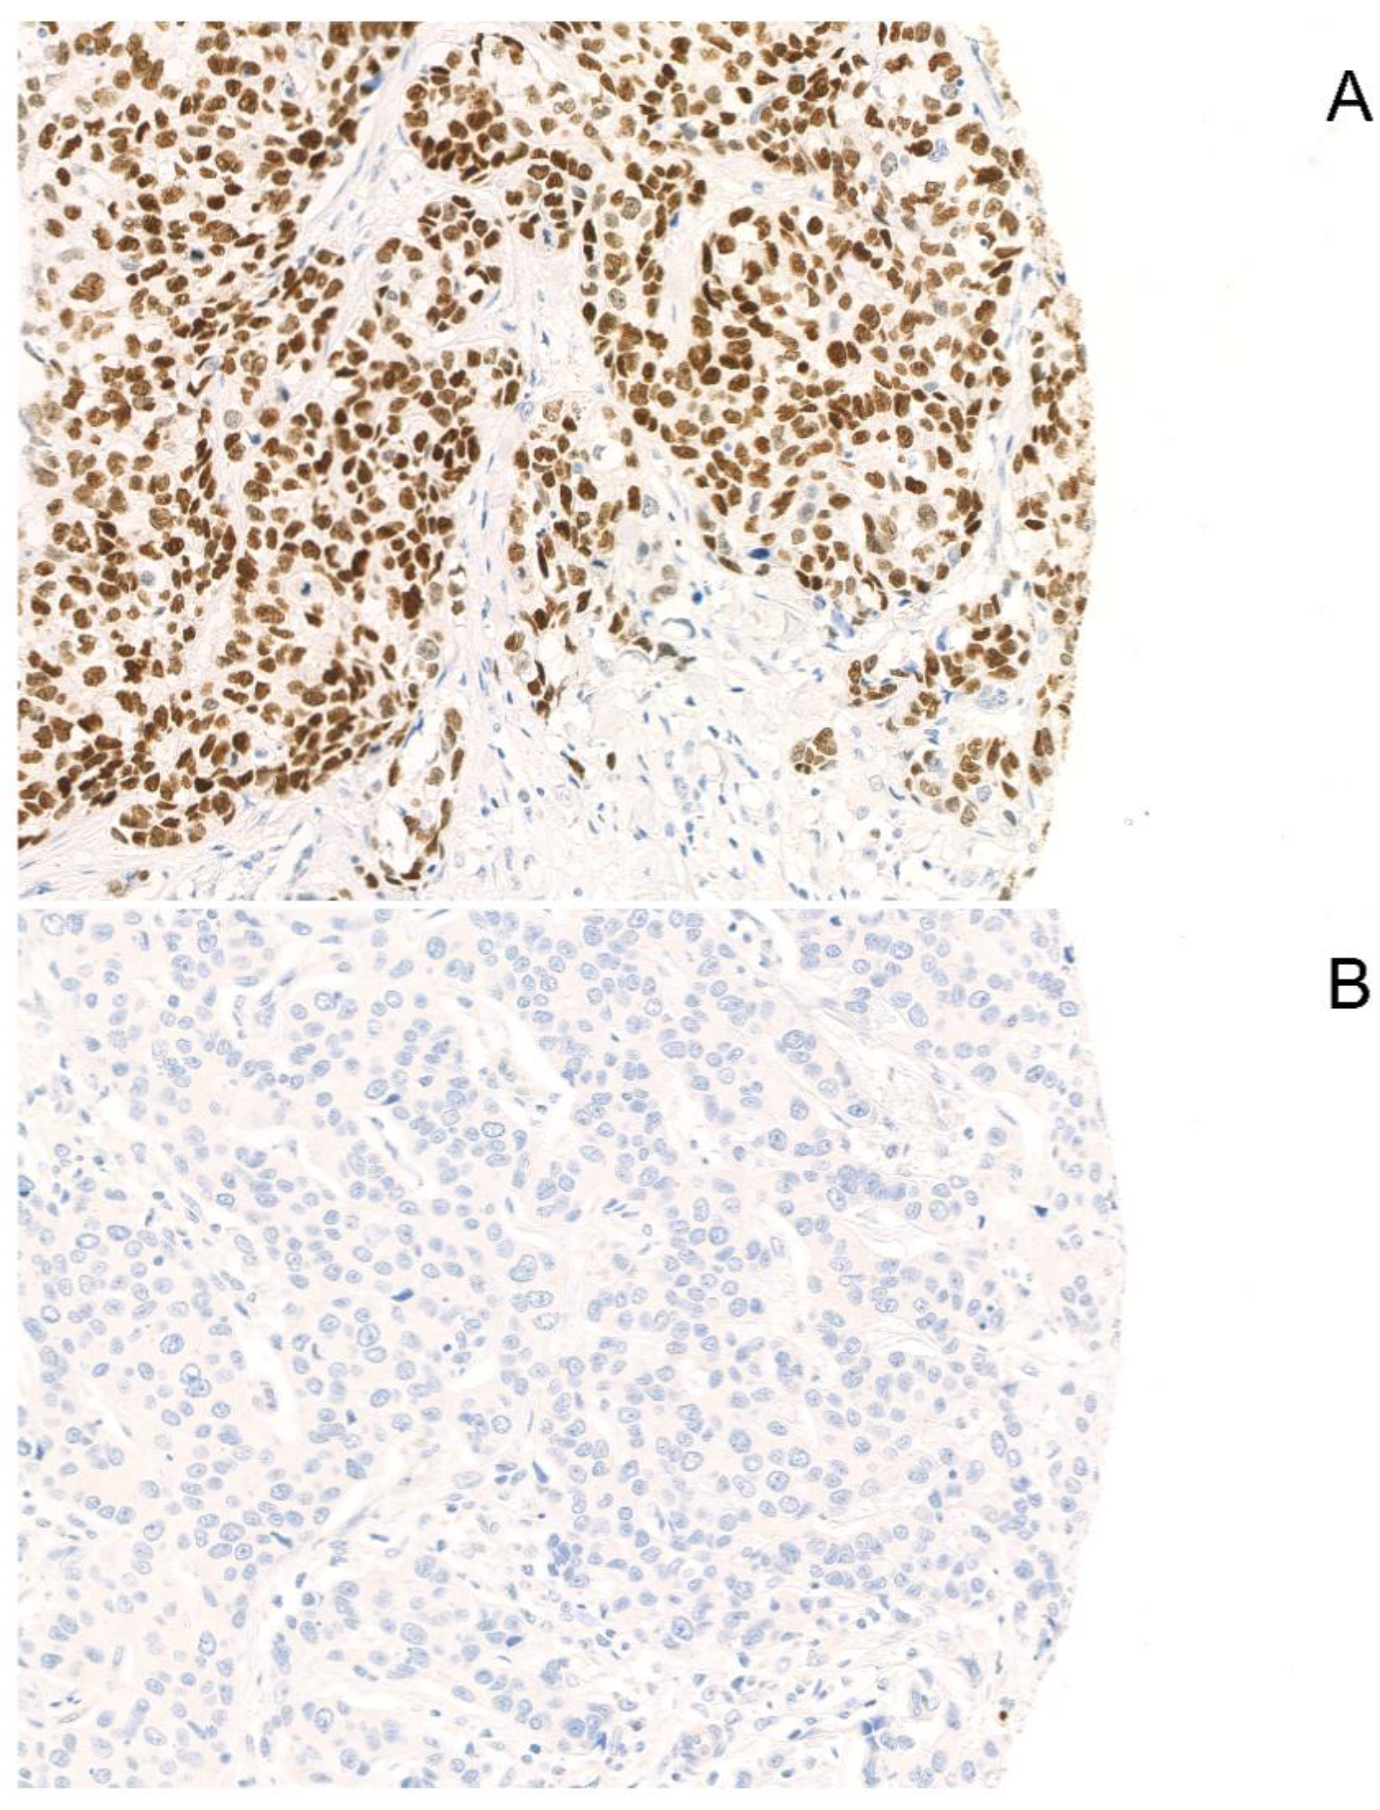

2.1. SOX-10 Positivity Is Associated with Low Tumor Size at First Diagnosis

4.2. Immunohistochemistry